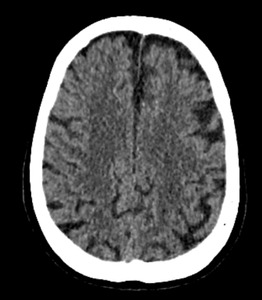

Echocardiography revealed a dilated left ventricle with a preserved left ventricular ejection fraction of 56%, without regional wall motion abnormalities. A repeat cranioencephalic CT was unremarkable. Arterial blood gas analysis indicated significant lactic acidosis, and blood tests showed isolated hyperamylasemia at 3540 units/liter. The infectious workup was negative. Abdominal ultrasound revealed liver congestion, along with dilatation of the inferior vena cava and suprahepatic veins. An abdominal CT scan, followed by exploratory laparotomy, did not reveal signs of acute pancreatitis or any other medical condition.